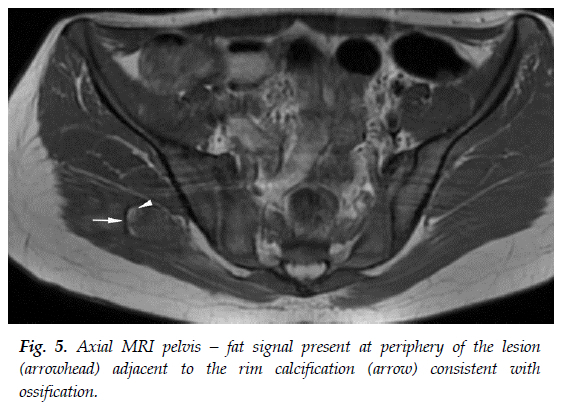

A follow-up MRI six months after diagnosis showed resolution of the surrounding oedema. The central lesion remained but with an increased rim of calcification and fat-based tissue (likely representing marrow fat related to developing ossification) immediately adjacent to the calcification (see Figure 4 and Figure 5). The lesion was slightly smaller in size compared to previous measurements (see Figure 2). Furthermore, there was no fluid in the sacroiliac joints, and no other abnormalities within the hip joint and bursae. These MRI findings corresponded with the evolution of the lesion from the subacute or intermediate phase to the chronic phase.